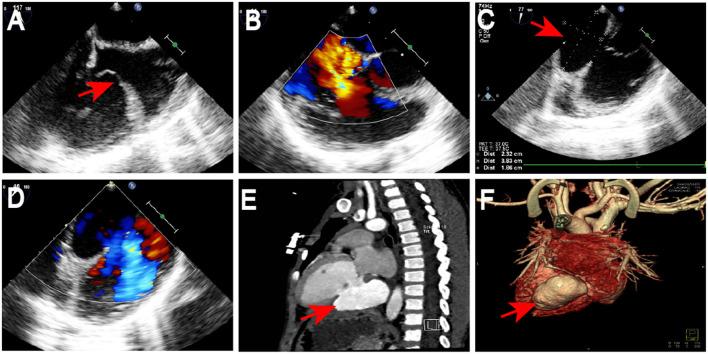

This case report is an extremely rare case of a traumatic left ventricular aneurysm in a 3-year-old child who also had tricuspid valve avulsion due to blunt trauma. The diagnostic findings and treatment protocols are discussed to provide a clinical reference.